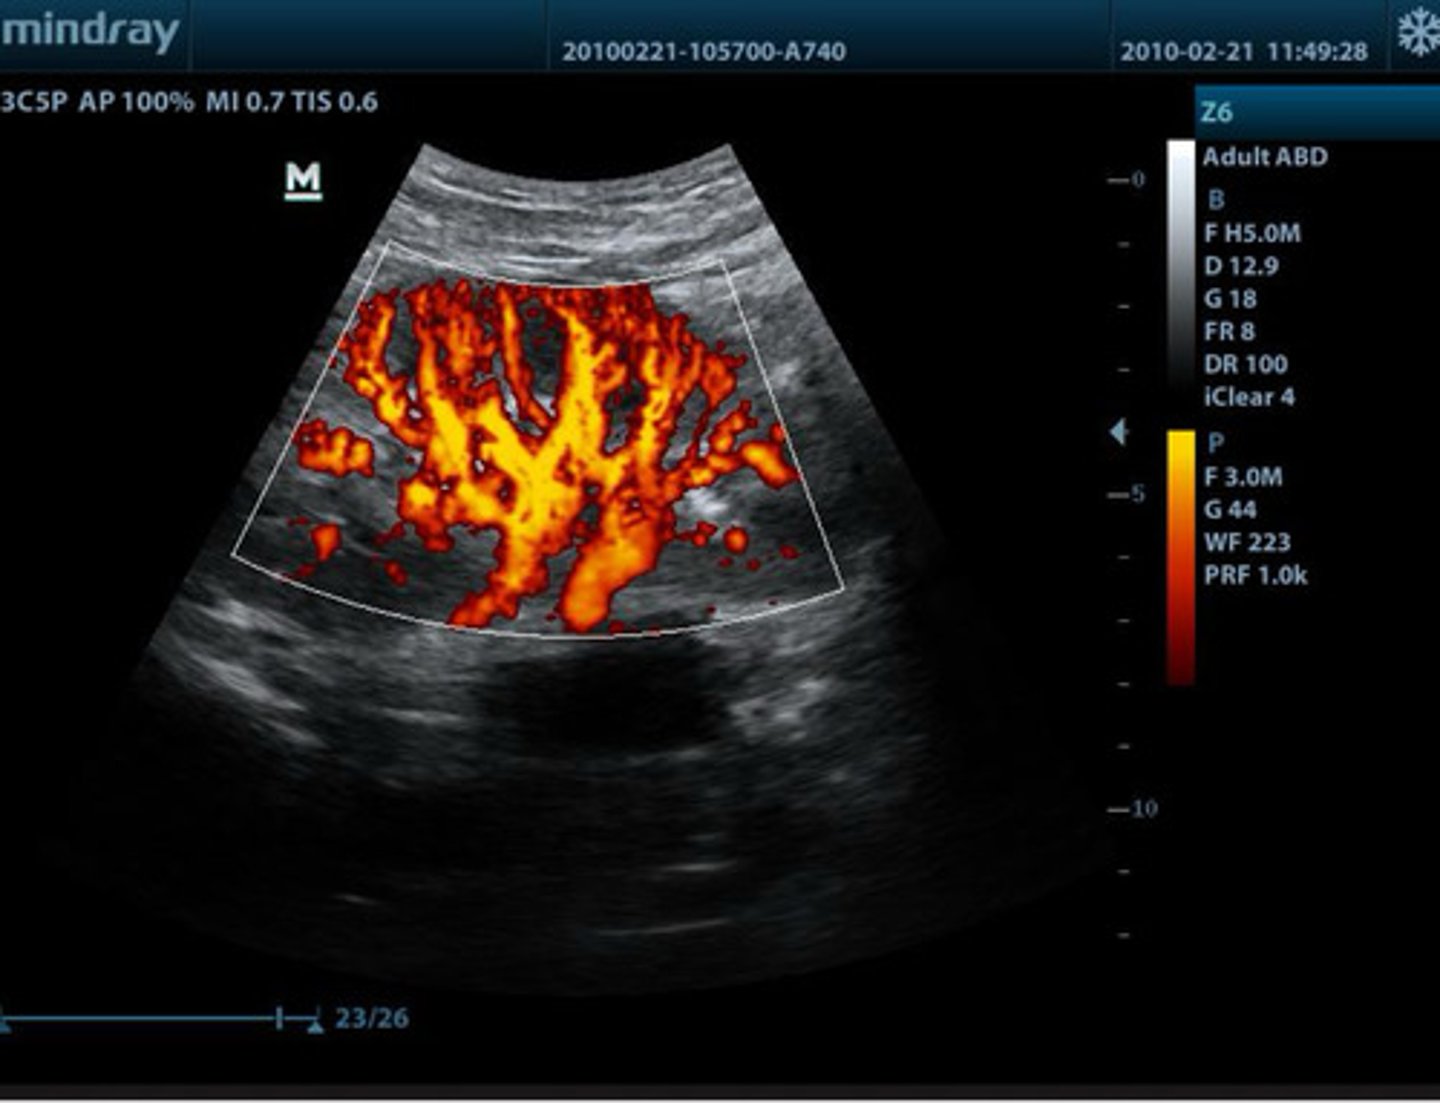

what type of doppler is this?